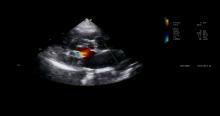

This video presents a repair of a mitral valve in a 73-year-old man with history of PND and one episode of pulmonary edema. The patient suffered from severe eccentric mitral regurgitation due to ruptured chordae and a thickened enlarged P2 segment.